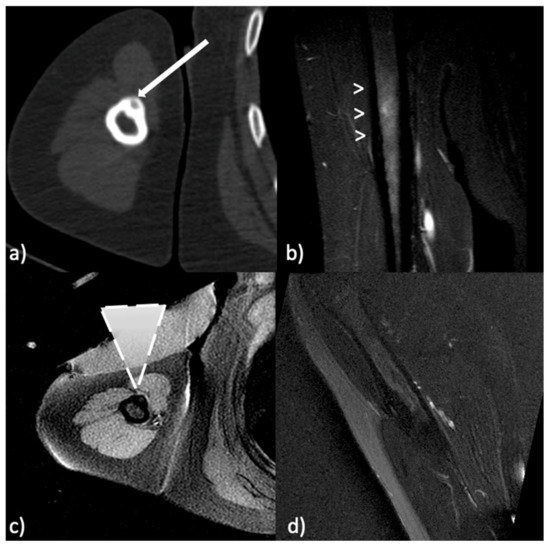

- Arrigoni, F.; Napoli, A.; Bazzocchi, A.; Zugaro, L.; Scipione, R.; Bruno, F.; Palumbo, P.; Anzidei, M.; Mercatelli, D.; Gravina, G.L.; et al. Magnetic-resonance-guided focused ultrasound treatment of non-spinal osteoid osteoma in children: Multicentre Experience. Pediatr. Radiol. 2019, 49, 1209–1216. [Google Scholar] [CrossRef] [PubMed]

- Geiger, D.; Napoli, A.; Conchiglia, A.; Gregori, L.M.; Arrigoni, F.; Bazzocchi, A.; Busacca, M.; Moreschini, O.; Mastantuono, M.; Albisinni, U.; et al. MR-Guided focused ultrasound (MRgFUS) ablation for the treatment of nonspinal osteoid osteoma: A prospective multicenter evaluation. J. Bone Jt. Surg. 2014, 96, 743–751. [Google Scholar] [CrossRef]

- Napoli, A.; Mastantuono, M.; Cavallo Marincola, B.; Anzidei, M.; Zaccagna, F.; Moreschini, O.; Passariello, R.; Catalano, C. Osteoid osteoma: MR-guided focused ultrasound for entirely noninvasive treatment. Radiology 2013, 267, 514–521. [Google Scholar] [CrossRef]